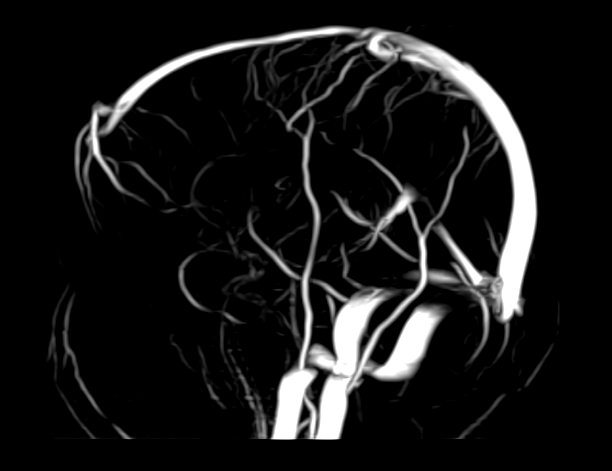

Магнитно-резонансная венография головного мозга позволяет детально изучить особенности анатомического и функциональной состояния венозного русла головного мозга. С помощью данного исследования можно исключить многие серьезные заболевания сосудов головного мозга и начать своевременное лечение.

Магнитно-резонансная томография вен применяется для диагностики широкого ряда заболеваний. В основе метода лежит воздействие магнитного излучения на ткани человека, что абсолютно безопасно и дает возможность с точностью визуализировать строение сосудов головного мозга.

По информативности МРТ артерий и вен головного мозга на шаг опережает традиционные способы диагностики с применением рентгеновских лучей или ультразвука. На МР-изображениях врачи-диагносты получают наглядную информацию о функционировании вен головного мозга.

МР-венография позволяет с высокой точностью определить:

• анатомический рисунок венозной системы;

• врожденные и приобретенные отклонения в строении и функционировании сосудов;

• нарушения трофики и оттока крови от отделов мозга;

• возможные повреждения сосудов и их последствия;

• наличие опухолевых образований, перекрывающих сосудистое русло.